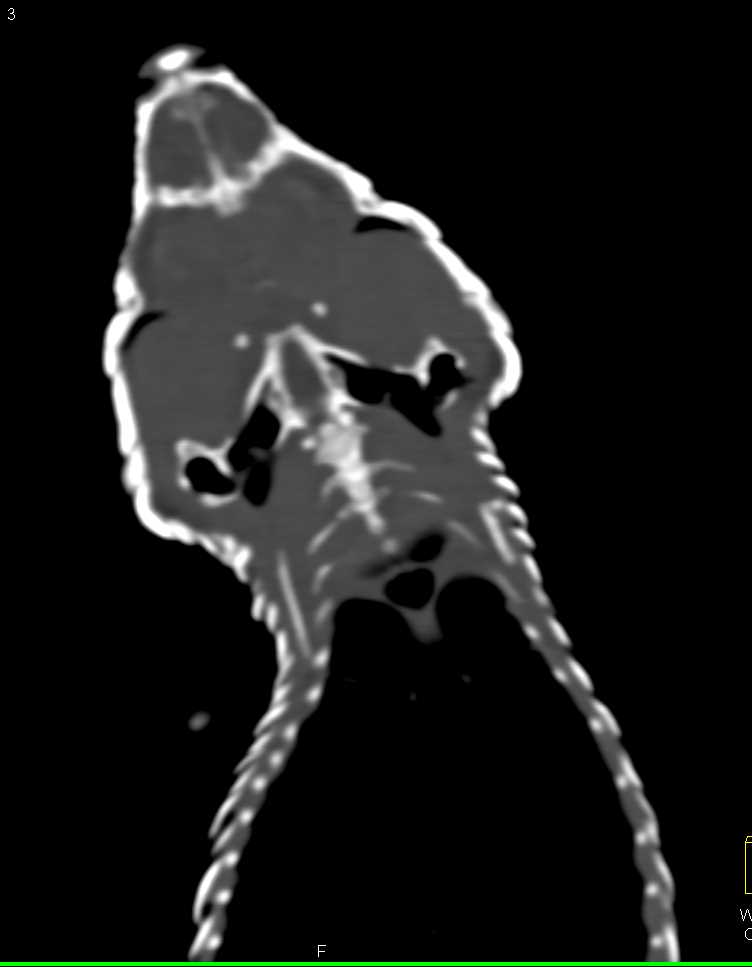

Blue Tongue Skink